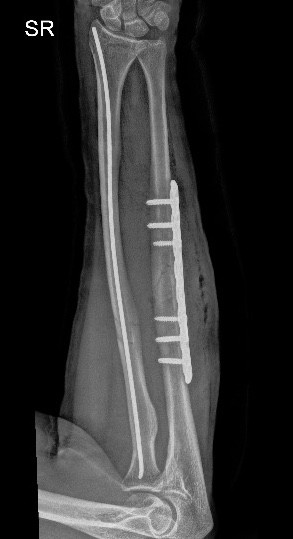

X-rays: To detect fractures or dislocations

Repair of fractures, dislocations, tendons, or ligaments

Fractures: Broken bones in fingers, metacarpals, or wrist